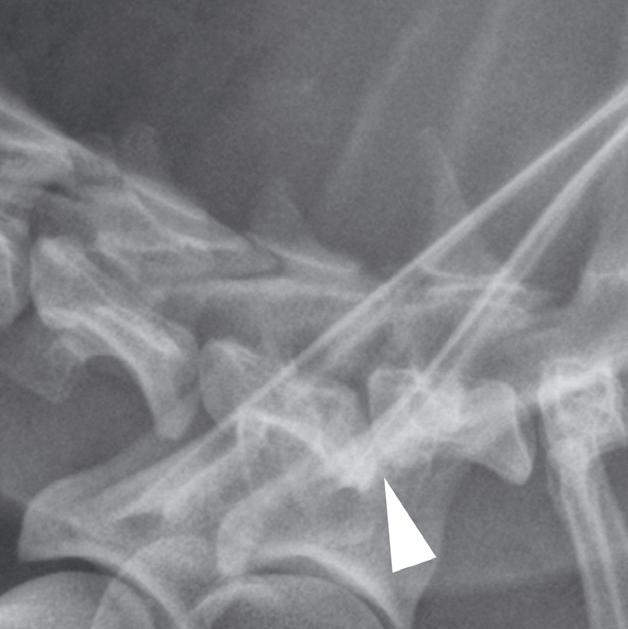

3.2.8. Podwichnięcie kręgów szyjnych ze złamaniem wyrostka stawowego (pies) TK i MR

Badania wykonano u 5-letniej samicy mieszańca w typie teriera, która została pogryziona w okolicy szyjnej przez większego psa tego samego dnia, w którym wykonano badania. Podczas wizyty u psa zaobserwowano deficyty neurologiczne z neuroanatomiczną lokalizacją w obrębie C6–T2. Radiogramy przeglądowe ukazały grzbietowe podwichnięcie kręgu C7 względem C6 oraz zwężenie przestrzeni międzykręgowej C6–C7 (a – grot strzałki). Podobne zmiany uwidoczniono na obrazach TK w projekcji strzałkowej i 3D (b, f – grot strzałki). Dodatkowo stwierdzono wieloodłamowe złamanie z przemieszczeniem prawego doczaszkowego wyrostka stawowego kręgu C7 (c–e – strzałka). Dla porównania przedstawiono prawidłowy lewy wyrostek stawowy (f – strzałka). W badaniu MR przestrzeń międzykręgowa C6–C7 była zwężona i wykazywała obniżoną intensywność sygnału w obrazach T2-zależnych (i – strzałka), a przemieszczony materiał dyskowy znajdował się w prawej dobrzusznej części kanału kręgowego (g, h – grot strzałki). W obrazach występują cechy ucisku na rdzeń kręgowy (g–i) oraz zwiększona intensywność sygnału w sekwencji T2-zależnej w obrębie rdzenia na poziomie C6–C7 (h, i), co wskazuje na jego uszkodzenie wewnętrzne. Materiał dyskowy został chirurgicznie usunięty z kanału kręgowego, a podwichnięcie zredukowano i ustabilizowano operacyjnie